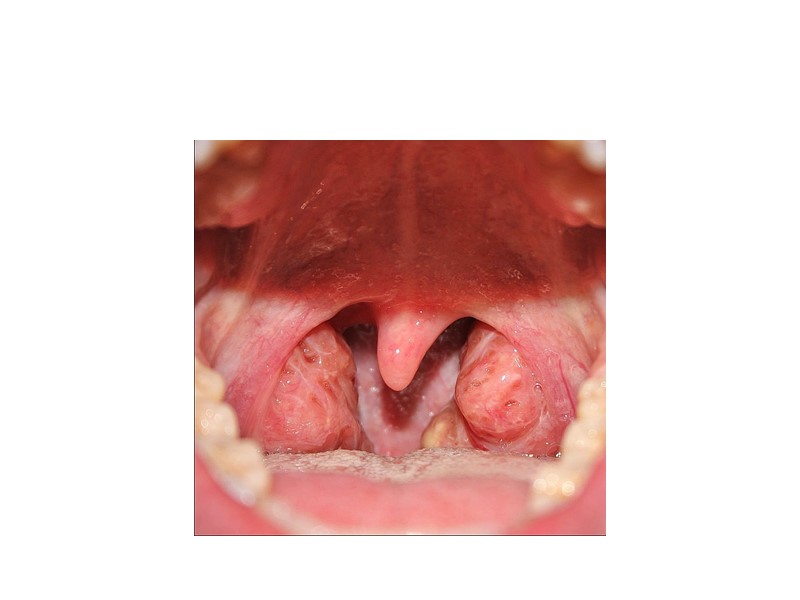

Ангины Дифтерию зева наиболее часто приходится дифференцировать с разными формами ангин.Фолликулярная ангина вызывается гемолитическим стрептококком. Общими признаками являются более острое чем при дифтерии начало болезни и большая выраженность воспалительных изменений в зеве в виде яркой гиперемии и рыхлости отека слизистой.

Лакунарную ангину дифференцируют с тонзиллярной формой дифтерии.При лакунарной ангине налет рыхлой консистенции и чаще сосредоточен в лакунах нередко гнойный не имеет характерной дифтерии тенденции к распространению. При дифтерии налеты в виде очень плотной фибринозной пленки. При лакунарной ангине быстрый эффект от терапии.

При некротической ангине гнойные налеты гиперемия в зеве выражен характер местных изменений значительно увеличены и болезненны шейные лимфатические узлы. Температура повышена до 40 градусов.Некротические пленки принимают за налеты они тоже серого цвета но находятся в глубине как бы минус ткань при дифтерии пленки на поверхности- плюс ткань.